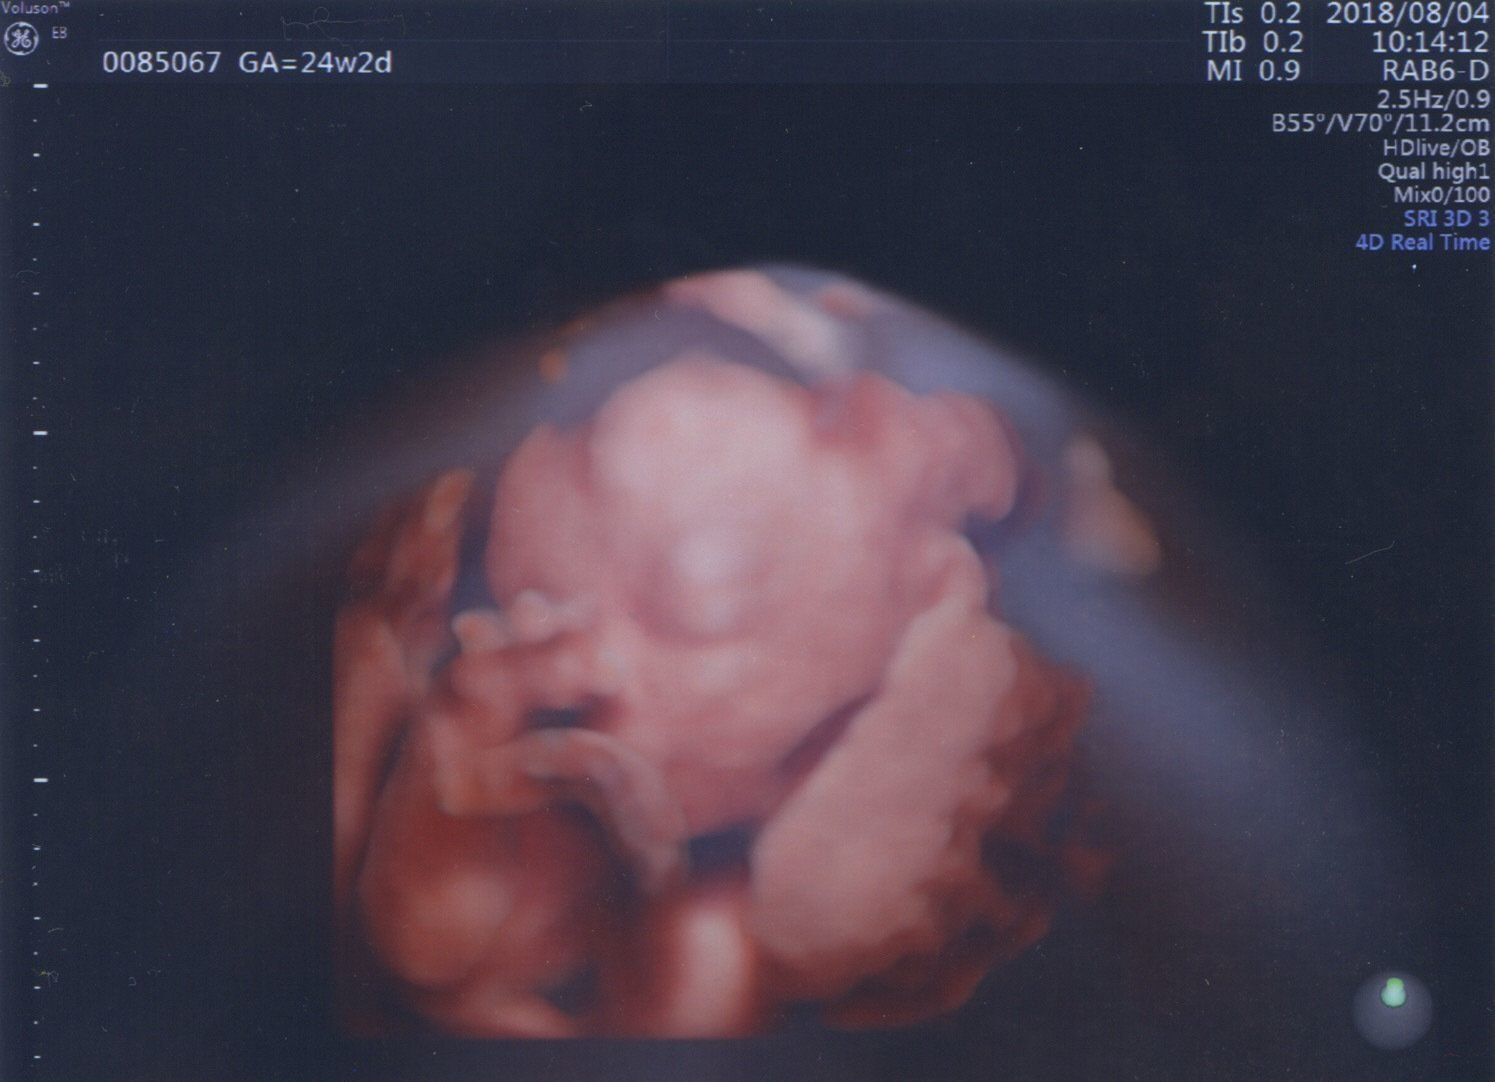

妊娠24週目 元気いっぱいに性別アピール!

妊娠24週目の健診で性別が判明!

エコーの最中に、私も夫もわかるように「男の子だよ」とアピールしてくれました。あまりにもはっきり見えたので、先生も「すぐにわかっちゃったね」と笑っていました。